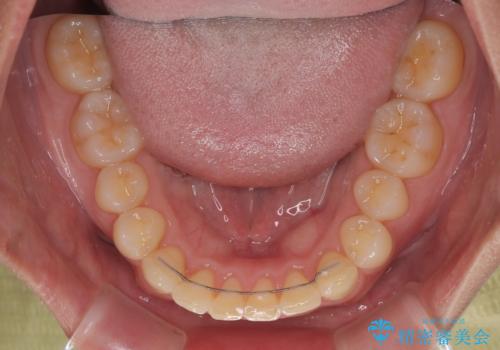

下顎臼歯を起き上がらせるためにユーティリティーアーチを使用し、一気に深い咬み合わせを改善することができました。